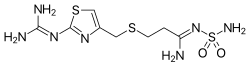

В 1975-м году появился циметидин («Smith Kline and French»), в 1979-м — ранитидин («Smith Kline and French»), в 1984-м — фамотидин («Merck»), в 1987-м — низатидин («Eli Lilly and Company», США). H2-блокаторы сразу стали «золотым стандартом» терапии кислотозависимых заболеваний, а ранитидин к 1988 году — наиболее продаваемым рецептурным препаратом и оставались ими до появления ингибиторов протонного насоса (омепразола).

Ранитидин имеет меньше типичных для циметидина побочных эффектов, а препараты последующих поколений — ещё меньше. При этом активность фамотидина в 20—60 раз превышает активность циметидина и в 3-20 раз активность ранитидина. По сравнению с ранитидином фамотидин более эффективно повышает pH и снижает объем желудочного содержимого. Длительность антисекреторного действия ранитидина — 8-10 часов, а фамотидина — 12 часов[1].

H2-блокаторы IV и V поколений низатидин и роксатидин на практике мало чем отличаются от фамотидина и не имеют перед ним существенных преимуществ, а роксатидин даже немного проигрывает фамотидину в кислотоподавляющей активности[4].